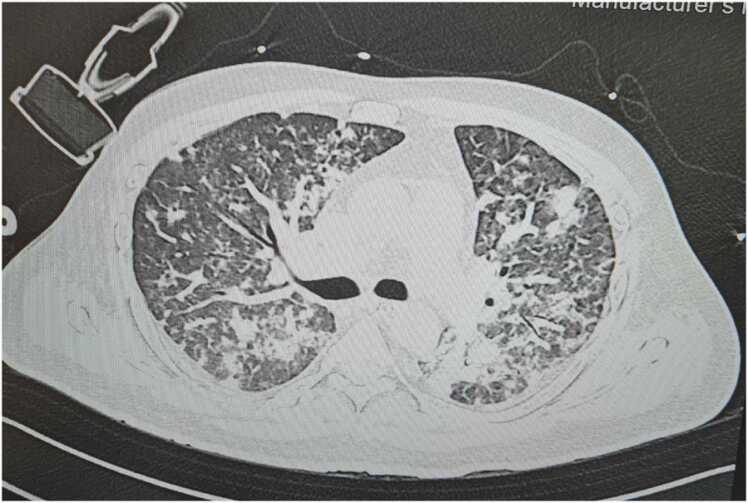

On arrival to ICU he was started he was started on NIV support in view of respiratory distress and low saturation with settings of FiO2 0.8, PEEP 8 cm H2O and PS above PEEP 12 cm H2O. Urgent USG abdomen showed hepatomegaly with right lobe live liver abscess and splenic abscess. Provisional diagnosis of sepsis with MODS (? Melioidosis) with diabetic ketoacidosis was made. Blood, urine, sputum cultures were sent before starting the antibiotics. The patient was started on meropenem, metronidazole, teicoplanin, doxycycline, low molecular weight heparin (LMWH) and i.v. insulin infusion. Further investigations showed areas of consolidation and diffuse ground glass opacities in bilateral lung fields in HRCT chest (Fig. 1). CECT abdomen revealed multiple liver abscess in right lobe of liver, multiple splenic abscesses with hepatosplenomegaly (Fig. 2). Diagnostic tap of liver abscess was sent to confirm the diagnosis and ensure long term compliance of the patient with the oral antibiotics to be given for the eradication regime of Burkholderia pseudomallei.

Fig. 2.

CECT abdomen of case 1- Multiple liver abscess in right lobe of liver, multiple splenic abscess.